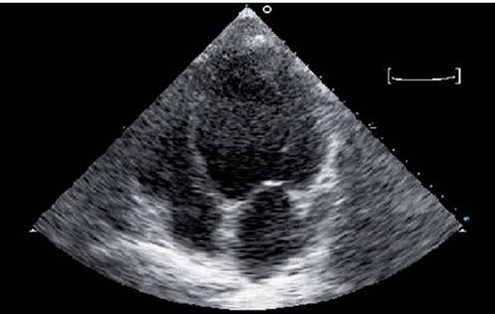

Es de extraordinaria utilidad para el diagnóstico de insuficiencia cardiaca. Permite valorar la masa ventricular, el tamaño de las cámaras cardiacas, la función sistólica y diastólica y detectar causas con tratamientos específicos. También permite evaluar la respuesta al tratamiento (mejora de la fracción de eyección y del remodelado).

Imagen apical de 4 cámaras de un corazón insuficiente y dilatado.